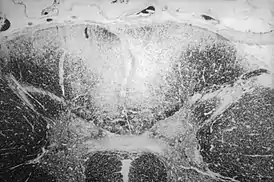

Гуммы головного мозга встречаются редко. Излюбленная локализация — основание мозга; реже располагается в мозговом веществе. Приводит к повышению внутричерепного давления. Клиническое течение напоминает таковое при опухоли мозга, с которой и следует проводить дифференциальный диагноз. Гумма спинного мозга чаще локализуется в шейном или среднегрудном отделе[55][56].